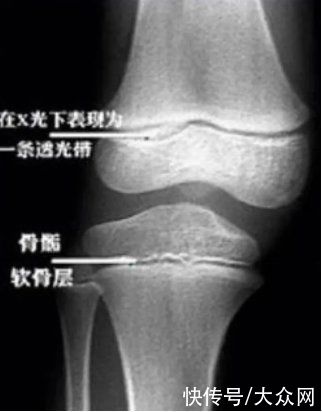

几乎没有产品会对增高有用,尤其是对成年人,因为骨骺线闭合之后,骨骼不会再增长,长高的空间也消失了。虽然对于想要再长高的人群来说,这是一个残酷的结论,但是这就是事实。人在青春期时,身高的增长非常快。长高的原因主要是骨骼发育中表现的长度增长。孩子能不能长高,与骨骼的生长发育潜力有非常密切的关系,而骨骺线就是一个非常重要的标志。骨头增长就像是盖摩天大楼,在盖之前需要有足够高度的脚手架才能搭建大楼的主体结构。其中,软骨基质就是骨骼生长的“脚手架”,通过脚手架,工人们(成骨细胞)带着原料(蛋白、矿物质等)顺着楼梯(血管)一级级往上建造着高楼。软骨细胞不断增生同时又被不断骨化,使得骨的长度不断地增加。这个工程会一直进行到成年期的初期(约18岁),摩天大楼的建造也就接近了尾声,脚手架需要慢慢地清空,楼梯也会一级级回收,盖楼的速度也会越来越慢。

回到微观骨骼上来看,这时候骨骺板(富含有血管的软骨生长板)会被骨组织取代,成为残余下来的骨骺线,骨干也就停止增长了。